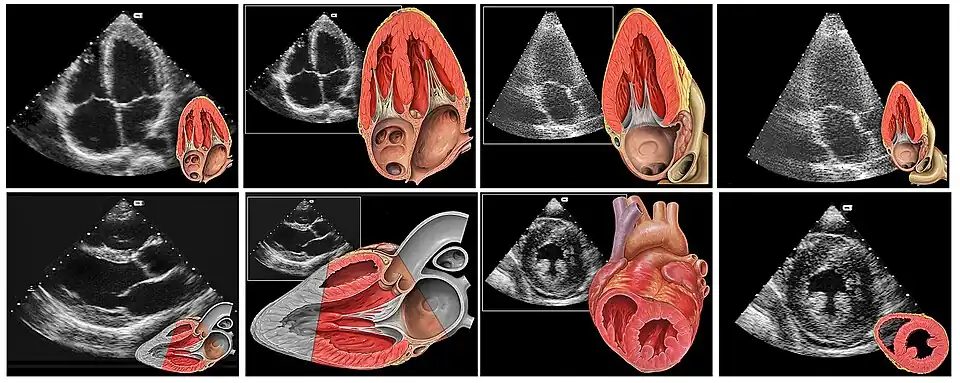

Echokardiografia, echo serca, USG serca, ultrasonokardiografia – UKG – technika diagnostyki obrazowej polegająca na badaniu struktur serca i dużych naczyń krwionośnych za pomocą ultradźwięków (ultrasonografia). Zwykle stosuje się ultradźwięki o częstotliwości od 1 do 10 MHz. Na ekranie monitora uzyskuje się obraz powstający w wyniku odbicia fali ultradźwiękowej od badanych struktur. Obraz można zarejestrować na płycie DVD lub wydrukować.

Badanie to umożliwia w sposób nieinwazyjny ocenę struktur anatomicznych serca, a także ocenę ruchu mięśnia sercowego i zastawek wewnątrzsercowych oraz przepływ krwi w obrębie przedsionków i komór serca, dużych naczyń sercowych (aorta, żyły główne, tętnica i żyły płucne) i naczyń wieńcowych. Stosuje się różne systemy echokardiograficzne (echokardiografia jedno-, dwu- i trójwymiarowa oraz dopplerowska)[1].

To badanie wykonywane poprzez ścianę klatki piersiowej, umożliwiające obrazowanie serca w badaniu:

- dwuwymiarowym (2D) – umożliwiającym pomiary powierzchni i objętości oraz obliczenie frakcji wyrzutowej[1];

- trójwymiarowym (3D) – umożliwiającym ocenę struktur serca w perspektywie (obraz przestrzenny), co umożliwia dokładną ocenę serca w przypadku wad serca przed zabiegami kardiochirurgicznymi;

- dopplerowskim – opartym na wykorzystaniu zjawiska Dopplera, umożliwiającym pomiar prędkości ruchu elementów odbijających emitowaną wiązkę ultradźwięków, np. szybkość przepływu krwi i gradient ciśnień przez zastawkę aortalną[1][2].